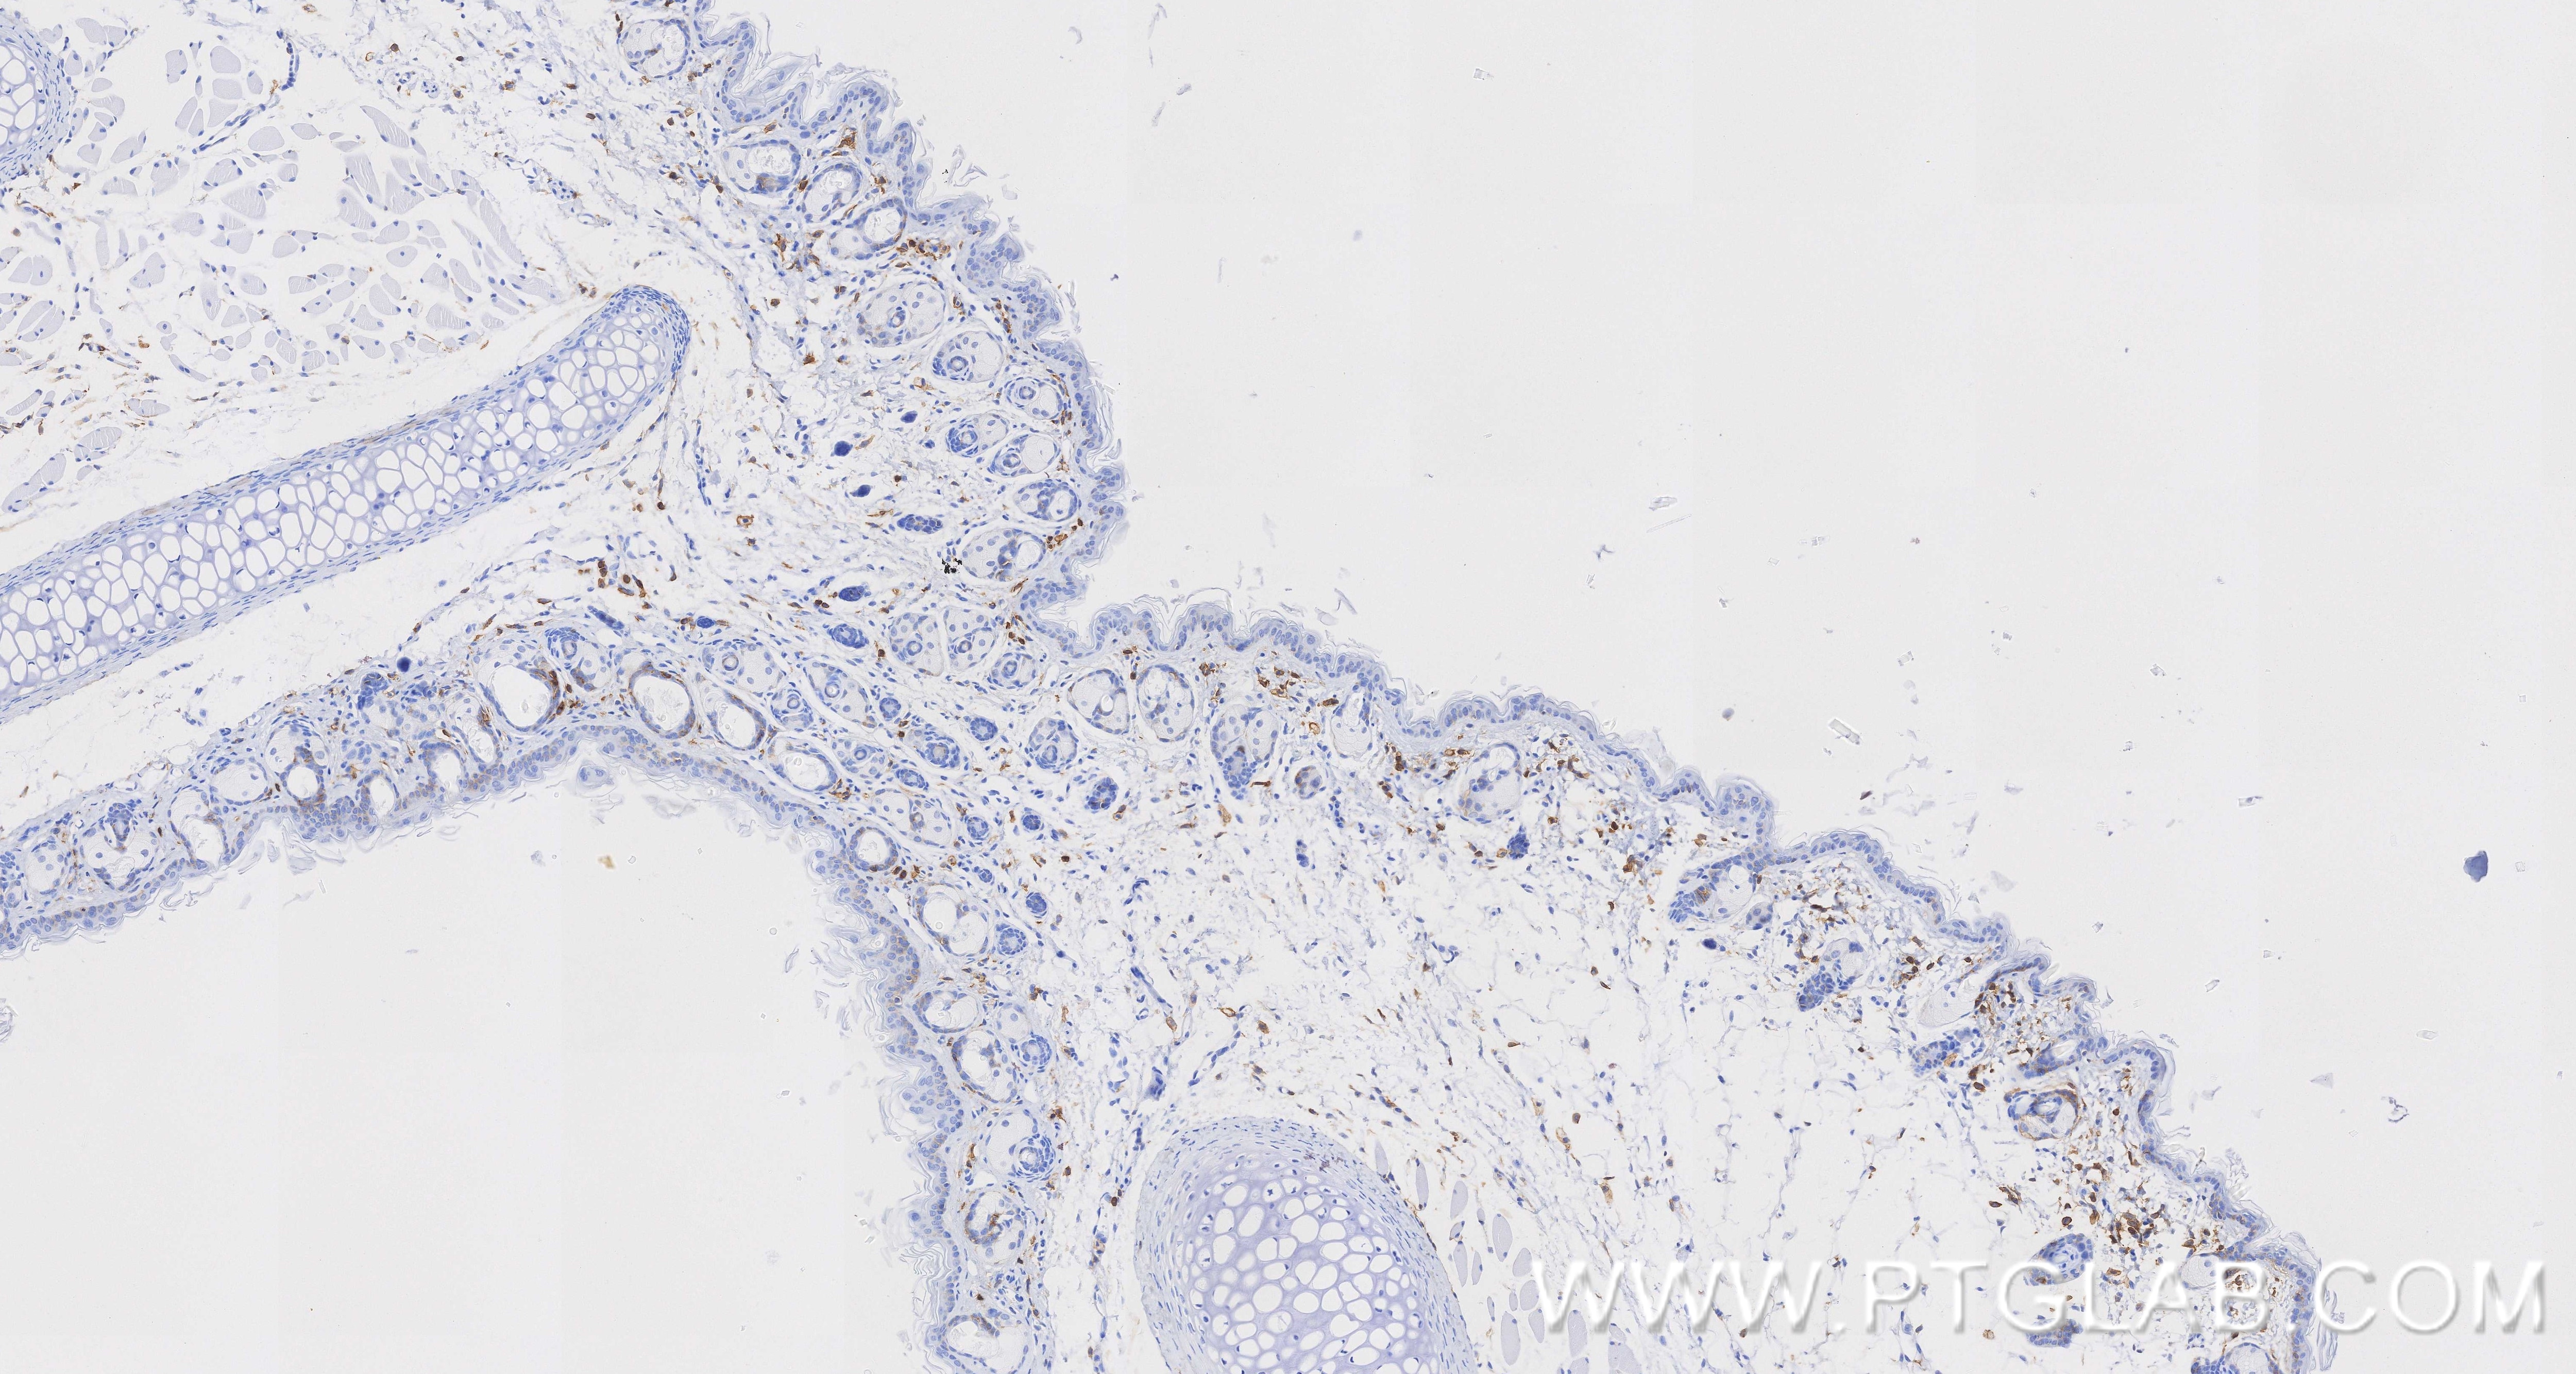

85163-5-PBS targets CD44 in WB, IHC, IF/ICC, Indirect ELISA applications and shows reactivity with human, mouse samples.